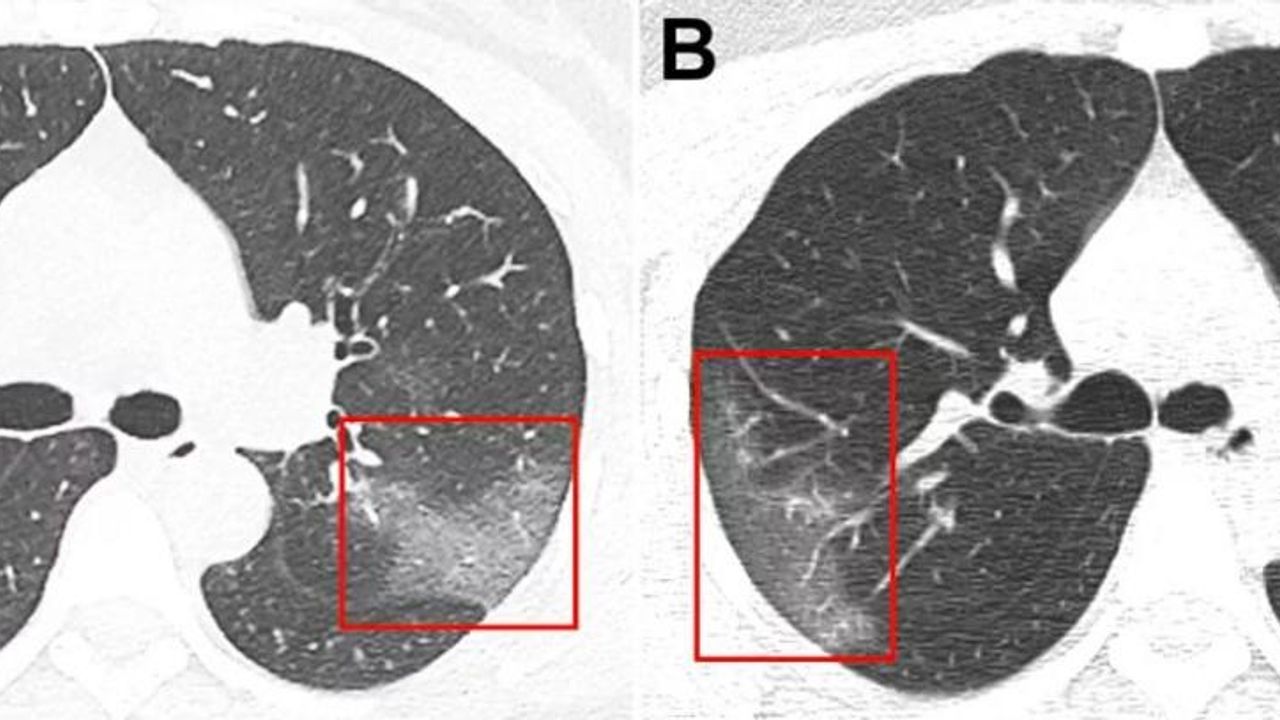

Кт Легких Матовое Стекло Фото

Кт Легких Матовое Стекло Фото 108 фото